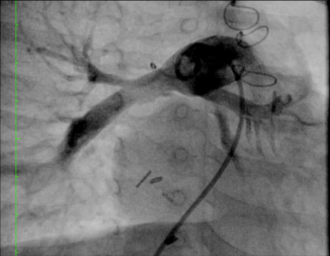

MAPCA症例 4本のMAPCAが有する症例

肺動脈統合術(unifocalizaton)術後 矢印の部分が狭窄病変

術後5ヵ月で肺動脈の狭窄に対してカテーテル治療を行った後の血管造影